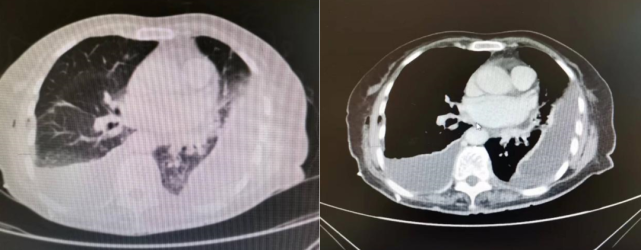

6月19日胸部CT ↑

2022年7月8日,患者再次感到胸闷加重,至我院门诊查胸部+上腹部CT,提示双侧胸腔积液(左肺部分包裹性积液)伴邻近肺组织膨胀不全,对比其6月19日的胸部CT,发现右侧胸腔积液较前增多,患者两肺散在条索影伴渗出较前进展。发现胆囊底部软组织结节,这时团队首先想到了是否为胆囊腺肌症?并且患者的肝脏、脾脏及左肾有钙化灶。为了进一步明确胸腔积液病因诊断,门诊以「胸腔积液病因待查」收住科室。整个病程中,患者无畏寒、寒战,无胸痛,无咳嗽咳痰、咯血、腹痛、腹泻。发病以来,精神尚可,二便正常,体重未见明显变化。